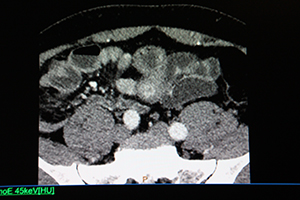

神経内分泌腫瘍(NET)症例の通常画像。大腸に複数の造影効果が認められる。 |

同一症例の仮想単色X線画像(45keV)。通常画像よりも明瞭に,複数の造影効果が認められる。 |